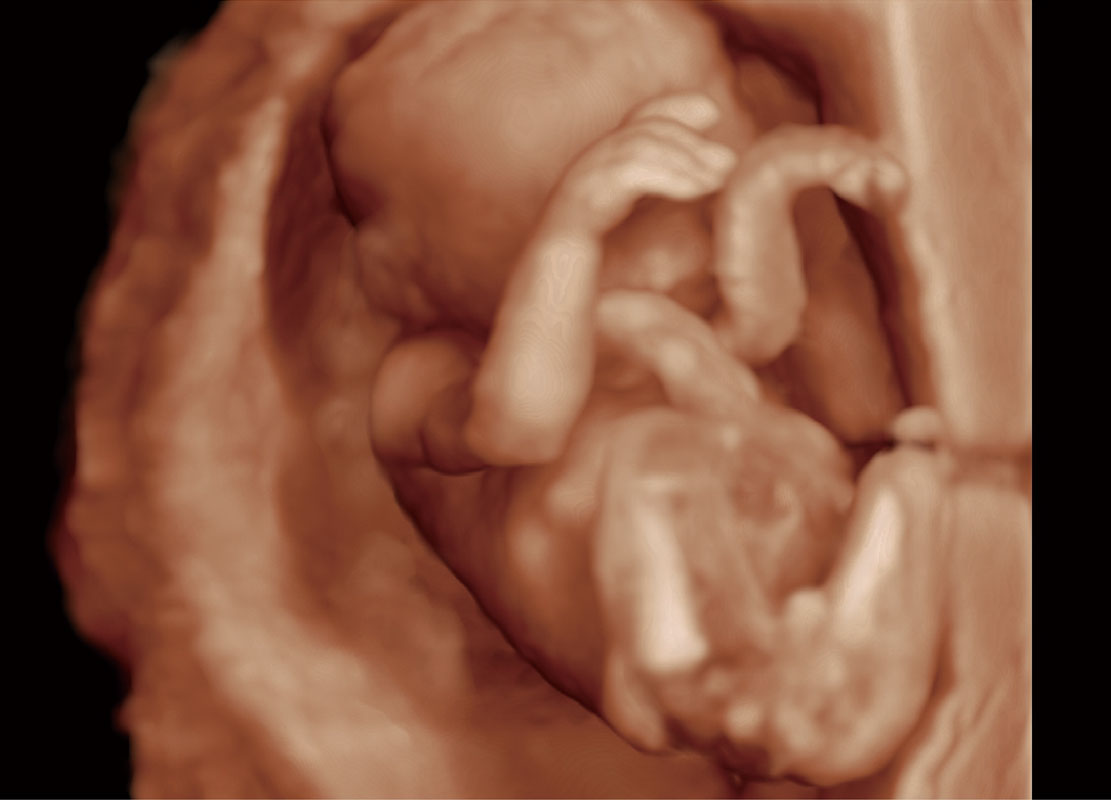

高分辨率容积成像-早孕胎儿

P60提供简单易学易用的高端诊断工具,为您中晚孕筛查提供快速清晰的解剖信息。

S-Fetus能够助您在实时扫查过程中自动识别标准切面、自动测量并录入报告。一个按键,即可快速、高效地获取胎儿生理指标,简化您的产科检查操作。